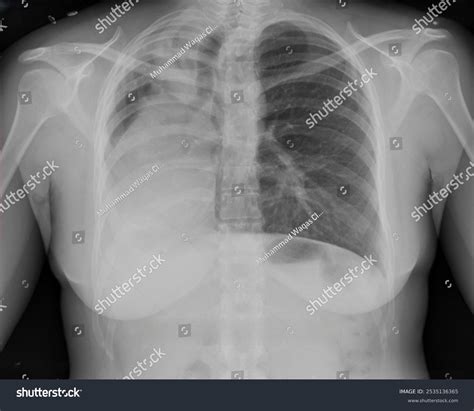

Consolidation refers to the replacement of air in the lungs with fluid, cells, or other material. It appears as an area of increased opacity on the X-ray. Common causes include pneumonia and pulmonary edema.

Case Study 3: Heart Failure

A 70-year-old patient with a history of hypertension presents with shortness of breath and peripheral edema. The chest X-ray shows cardiomegaly and pulmonary edema. An echocardiogram confirms the diagnosis of heart failure, and the patient is started on diuretics and other medications to manage the condition.